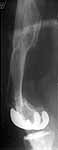

A male 41 years old transferred to our unit with 3 week old femoral fracture near the knee prosthesis after a mimimal fall. In 1994 he sustained multiple injury with open patella fracture (complicated with septic arthritis), and ipsilateral femoral shaft fracture treated by ex-fix.

TKA performed in 1998. In 2001 he got a periprosthetic fracture which was treated nonoperatively and healed with ~1 cm dorsal displacement of the distal femoral block. Knee ROM prior the recent injury was about 90-95 degrees. He didn't use walking aid.

Images attached.